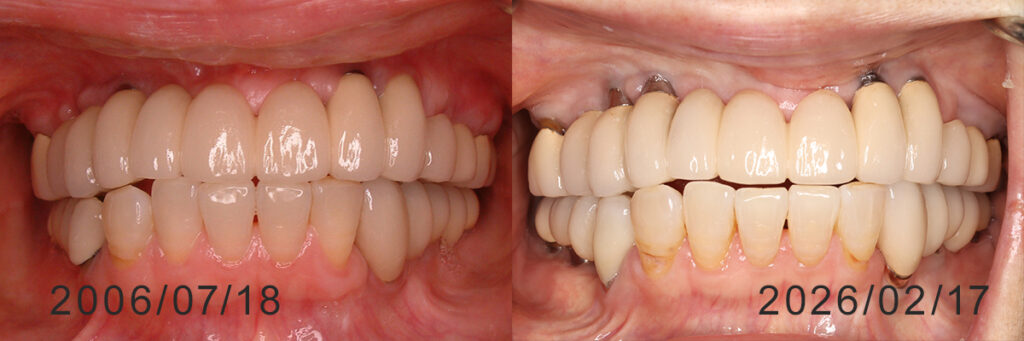

ピンクセラミックで歯肉形態付与(25年経過)

下は保存不能歯を逐次インプラントに置き換え、仮修復をしながら約2年で最終的に全歯列の修復になったもの。 貴金属の内冠を利用。 鋳造誤差やポーセレン焼き付けによる収縮を補正する最後方歯のフレームは完成時にカット。 治療完了後18年経過

完成時前面観と内冠印象後の作業模型上のフレーム